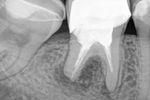

Orthograde Revision an Zähnen mit apikaler Aufhellung und Zustand nach Wurzelspitzenresektion.

Autor(en): Herrmann H-W.

Fundstelle: Endodontie 2007; 16: 321–328

Am Beispiel zweier Falldarstellungen werden die Möglichkeiten des Erhalts von Zähnen mit persistierender Parodontitis apicalis nach vorangegangener Wurzelspitzenresektion aufgezeigt. Durch den Einsatz moderner Behandlungsmethoden gelang es, die bereits als extraktionswürdig eingestuften Zähne zu erhalten.